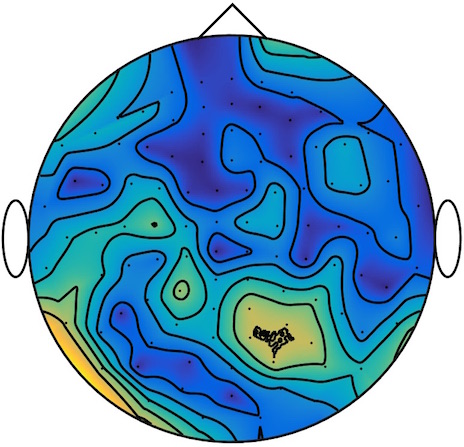

We applied our method to a magnetoencephalography (MEG) dataset. In this setup, brain activity of a subject is recorded (Elekta Neuromag, 306 sensors of which 204 planar gradiometers and 102 magnetometers, sampling frequency 1000Hz) while the subject reacted to the presentation of a target stimulus by pressing either the left or the right button.

Data is preprocessed applying signal space separation correction, interpolation of noisy sensors, and realignment of data into a subject-specific head position (MaxFilter, Elekta Neuromag). The signal was then filtered (low pass 40HZ), and artifacts such as blinks and heartbeats removed thanks to Signal-Space Projection using the Brainstorm software222http://neuroimage.usc.edu/brainstorm. The samples we used for our barycenter computations are an average of the norm of the two gradiometers for each channel from stimulation onto 50ms and the classes were left or right button.

| Class 1 | Class 2 | ||||||

|

|

|

|

|

|

|

|

| Sample 1 | Sample 2 | Sample 3 | Mean | Sample 1 | Sample 2 | Sample 3 | Mean |

|

|

|

|

|

|

|

|

This results in two classes of recordings, one for each pressed button. We aim at computing a representative activity map for each class using Wasserstein barycenters. For each class we have recordings each having samples located on the vertices of an hexahedral mesh of a hemisphere (corresponding to a MEG recording helmet). These recorded values are positive by construction, and we rescale them linearly to impose . Figure 6, top row, shows some samples from this dataset, displayed using interpolated colors as well as iso-level curves. The black dots represent the position of the electrodes on the half-sphere of the helmet, flattened on a 2-D disk.

We computed TV-regularized barycenters independently for each class by solving (16) with the TV regularization using the projected gradient descent method (22). We used a squared Euclidean metric (24) on the flattened hemisphere. Since the data is defined on an irregular graph, instead of (23), we use a graph-based discrete gradient. We denote the graph which connects neighboring electrodes. The gradient operator on the graph is

The total variation on this graph is then obtained by using , the norm, i.e. we use in (23).

Figure 6 compares the naive barycenters (i.e. the usual mean), barycenters obtained without regularization (i.e. ) and barycenters computed with an increasing regularization strength . The input histograms being very noisy, the use of regularization is important to make the area of significant activity emerge from the noise. The use of a TV regularization helps to keep a sharp transition between active and non-active regions.